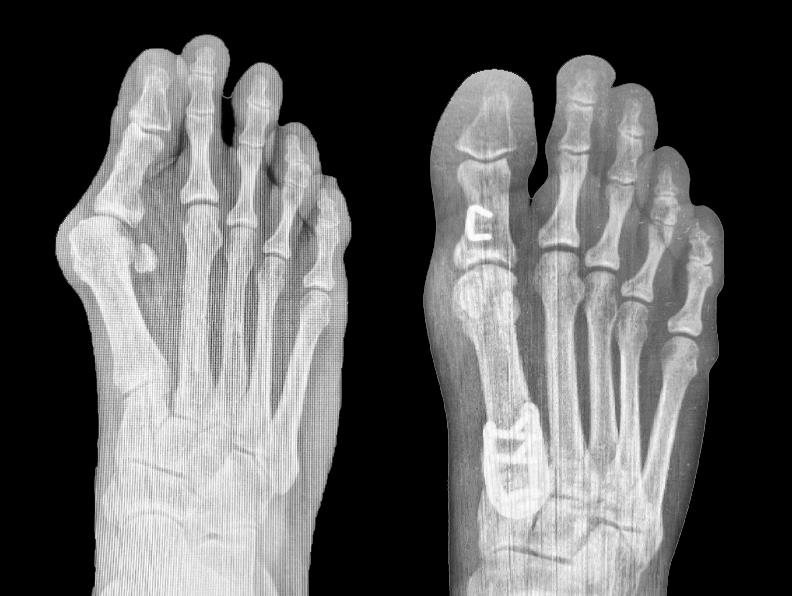

• LapiLock 4D Advanced Bunion Correction is described in manufacturer materials as a non-powered orthopedic manual bone positioner and jig system used for Lapidus bunion correction at the first tarsometatarsal joint, focusing on realigning and fusing the first metatarsal–medial cuneiform articulation rather than simply shaving the medial eminence.

• By shifting the correction proximally and addressing rotation, intermetatarsal divergence, and sagittal plane malalignment at the first tarsometatarsal joint, the system is intended to achieve a more anatomic and stable first-ray alignment than procedures that focus only on distal metatarsal osteotomy.

• LapiLock serves as a triplanar bone positioner and joint preparation system; definitive fusion of the first metatarsometatarsocuneiform joint is achieved with plate, screw, and staple constructs from the Fusion Orthopedics portfolio, selected at the surgeon’s discretion once correction is obtained.

• Manufacturer materials list 13 or more fixation options compatible with the system, including a U-Plate, a Neutral Lapidus Plate, Dual Slim constructs, T-Plate configurations, dual Lapidus plates, and two-plate constructs for more robust medial column constructs.

• Hallux valgus deformity commonly features an increased intermetatarsal angle between the first and second metatarsals, pronation of the first metatarsal around its longitudinal axis, and relative elevation or dorsiflexion of the first ray, with the sesamoid complex drifting lateral to the crista.

• Correcting at the first tarsometatarsal joint allows reduction of the intermetatarsal angle, restoration of sesamoid position under the metatarsal head, and re-establishment of a stable medial column, which can be more biomechanically advantageous than correcting only at the distal first metatarsal.